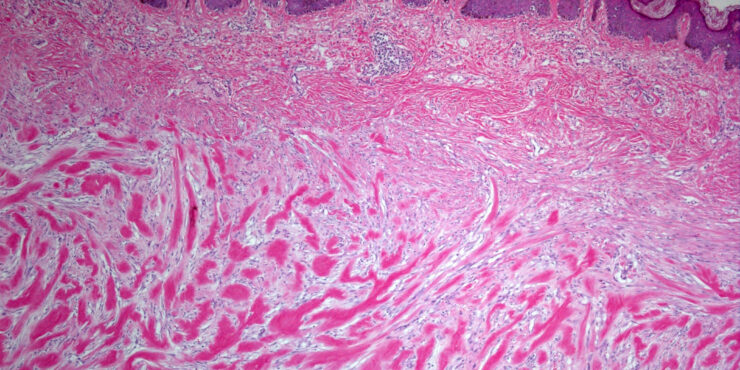

Kaposiform hemangioendothelioma =بطانوم وعائي دموي يشبه كابوزي OLYMPUS DIGITAL CAMERA OLYMPUS DIGITAL CAMERA OLYMPUS DIGITAL CAMERA Kaposiform Hemangioendothelioma KHE is a rare vascular tumor that has usually been reported in association with KMP. It may be present at birth or develop in early childhood. Rare adult cases have been reported. It may present as […]